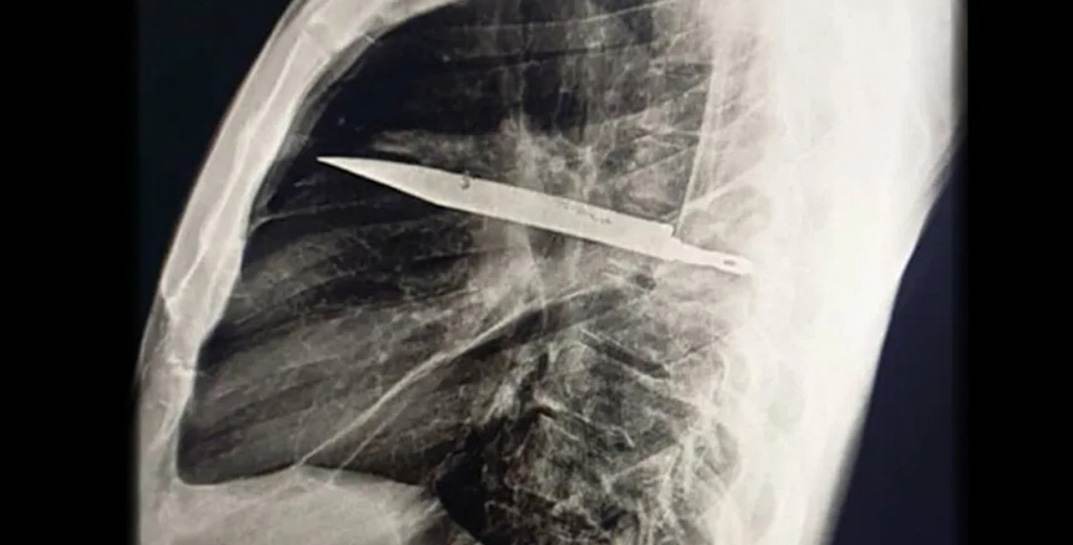

Пациент обратился в больницу с жалобой на нагноение в области груди. Обследование выявило шокирующую причину — крупное металлическое лезвие, которое находилось в груди мужчины. По словам пациента, 8 лет назад он стал участником потасовки, в ходе которой получил множественные ножевые ранения. Однако тогда его детально не осмотрели, оказав лишь поверхностную первую помощь.

Как показало обследование, организм мужчины смог адаптироваться к инородному телу, образовав вокруг него защитную капсулу из соединительной ткани. Очевидно, это и позволило мужчине прожить столько лет с лезвием ножа в груди, избегая серьёзных осложнений. По словам пациента, после той драки он не испытывал никаких проблем со здоровьем, и до недавних пор нож, оставшийся в теле, не давал о себе знать.

Хирурги провели операцию по извлечению лезвия, обработали рану и назначили антибиотики. Через десять дней пациент был полностью здоров и выписан из больницы. Медики отмечают, что раньше, если кому-то и приходилось жить с инородным телом долгие годы, то это чаще всего были какие-то осколки либо пули. Подобный случай с целым ножевым лезвием, так долго находившимся в организме, описан впервые.